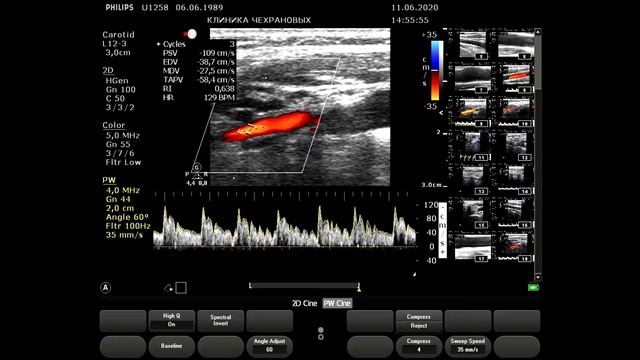

Болезнь отсутствия пульса. По научным данным данное заболевание встречается 26 случаев на 1 млн населения. В видео я ошибся говорю 3 случая на 100 тыс населения. Таким образом в Уссурийске где населения 200 тыс- это прям редкость просто я наблюдаю двоих таких пациентов и мне кажется чт они должны быть чаще. Коллеги вы встречали этот синдром в совей практике ? Итак пациентка прооперирована: протезирование левой общей сонной артерии по поводу окклюзии в 2022 году. В 2024 году возник рестеноз- в проксимальном сегменте возник гемодинамически значимый стеноз как подключичной артерии так и проксимального отдела шунта и мы наблюдаем коллатерализацию кровотока в левой подключичной артерии и разность АД а также снижение скорости и характера кровотока в протезе левой ОСА и в ВСА. Брахиоцефальный ствол также поражен но стеноз не более 40 незначимый. Правая общая сонная артерия идаельная ТИМ 045 мм. Вот такой случай. Наш whats app: 89143382293,